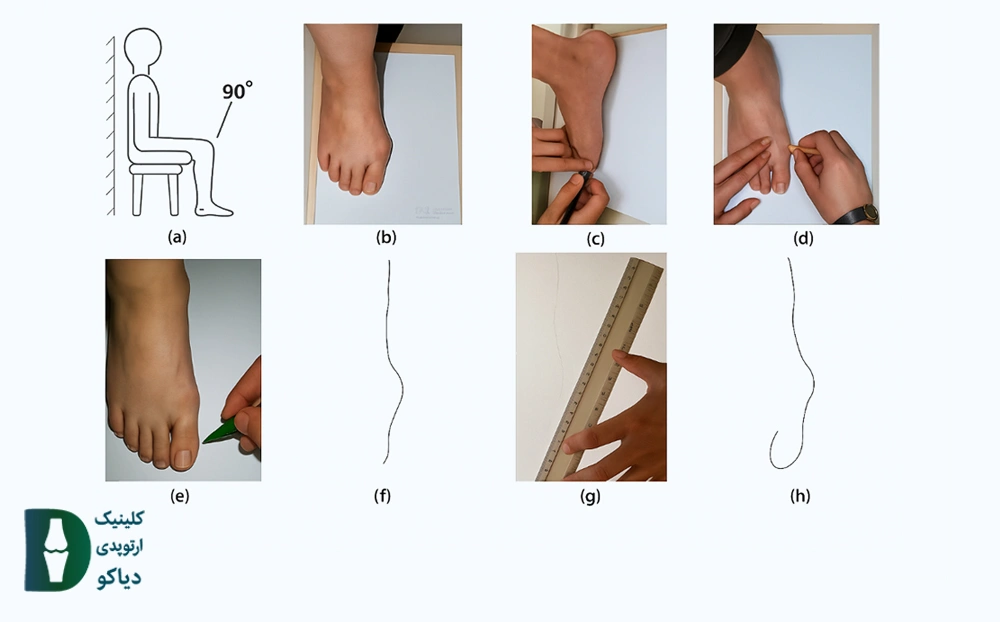

- آمادهسازی: روی یک صندلی بنشینید به گونهای که پای شما روی زمین قرار گیرد و زاویه زانو تقریباً ۹۰ درجه باشد (تصویر a).

- قرار دادن پا روی کاغذ: کاغذ سفید را زیر پای خود قرار دهید به گونهای که پای شما کاملاً روی آن جای بگیرد (تصویر b).

- ترسیم محیط پا: با استفاده از مداد یا خودکار، دقیقاً محیط بیرونی پای خود را در حالتی که کاملاً روی کاغذ ثابت است، ترسیم کنید (تصاویر c, d, e).

- مشخص کردن خطوط برای سنجش زاویه (اضافه شده برای کجی شست):

- پس از اتمام ترسیم، یک خط مستقیم فرضی یا قابلمشاهده را از مرکز مفصل مچ پا (جایی که ساق پا به پا متصل میشود) تا مرکز پاشنه پا رسم کنید. این خط، محور طولی پا در نظر گرفته میشود.

- سپس، یک خط مستقیم دیگر را از مرکز مفصل شست پا (مفصلی که شست را به بقیه پا وصل میکند) به سمت نوک انگشت شست (مرکز نوک شست) رسم کنید.

- اندازهگیری زاویه: با استفاده از یک نقاله، زاویه بین دو خطی که در مرحله قبل رسم کردید را اندازهگیری کنید. این زاویه، میزان انحراف شست شما را نشان میدهد.